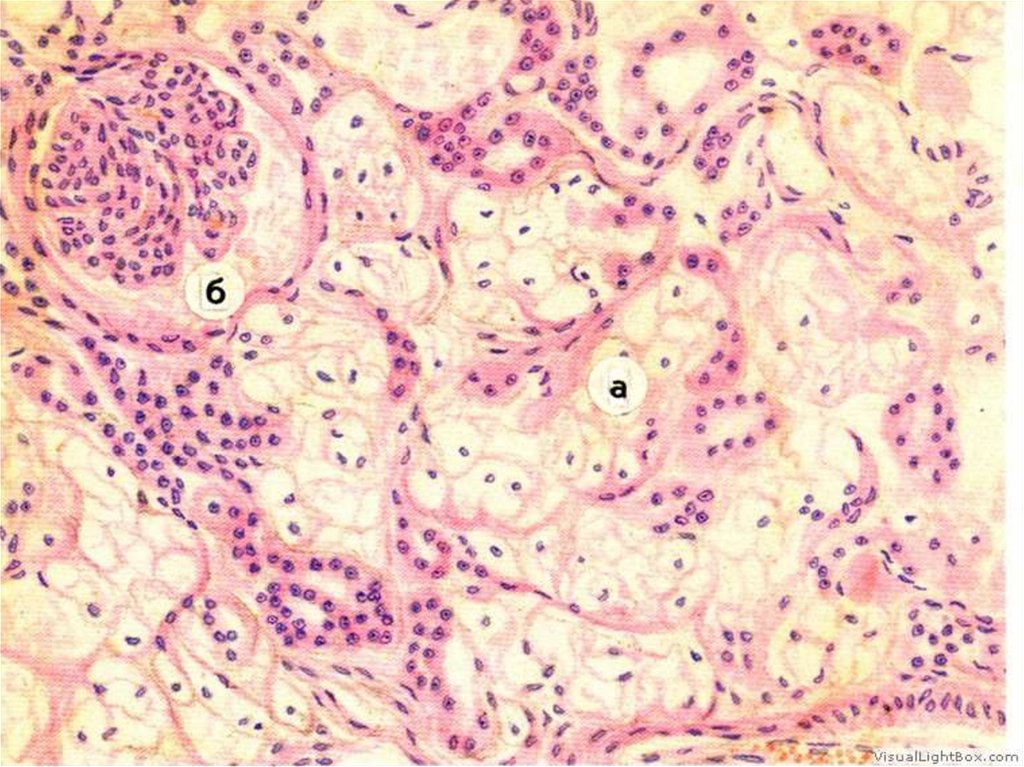

Гиалиноз сосудов и белых

тел в яичнике

1

2

2. Гиалиноз сосудов и клубочков почки. 1- гиалинизированный клубочек,

2 – мелкая артерия с гиалинозом.